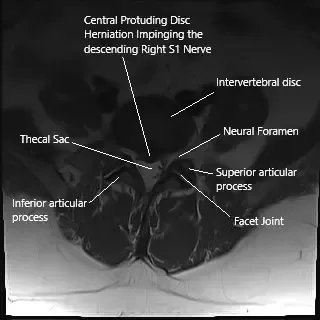

Axial section of the spine on MRI showing herniated intervertebral disc.

Diagnosis is typically clinical, based on a patient’s history and physical examination. Imaging tests like MRI are crucial for identifying disc herniations, degenerative changes, and other structural abnormalities in the lumbar spine. MRI scans in sagittal and axial views provide detailed images of the disc space, nerve roots, and the surrounding structures, helping guide treatment decisions.

The spine consists of vertebrae separated by intervertebral discs, which cushion and stabilize the spine. The nerve roots exit the spinal cord through the intervertebral foramen. The lumbar spine, in particular, is prone to disc herniation due to its weight-bearing function. The sciatic nerve, originating from the lumbar and sacral spinal roots, runs through the pelvis and down the legs, providing motor and sensory function.

The most common cause of sciatica is a herniated lumbar disc, where the disc material presses on the nerve root. Other causes include degenerative changes such as facet arthritis, spinal stenosis, or osteophyte formation. Sciatica can also result from synovial cysts or trauma. These conditions irritate or compress the nerve roots, leading to inflammation, ischemia, and pain.